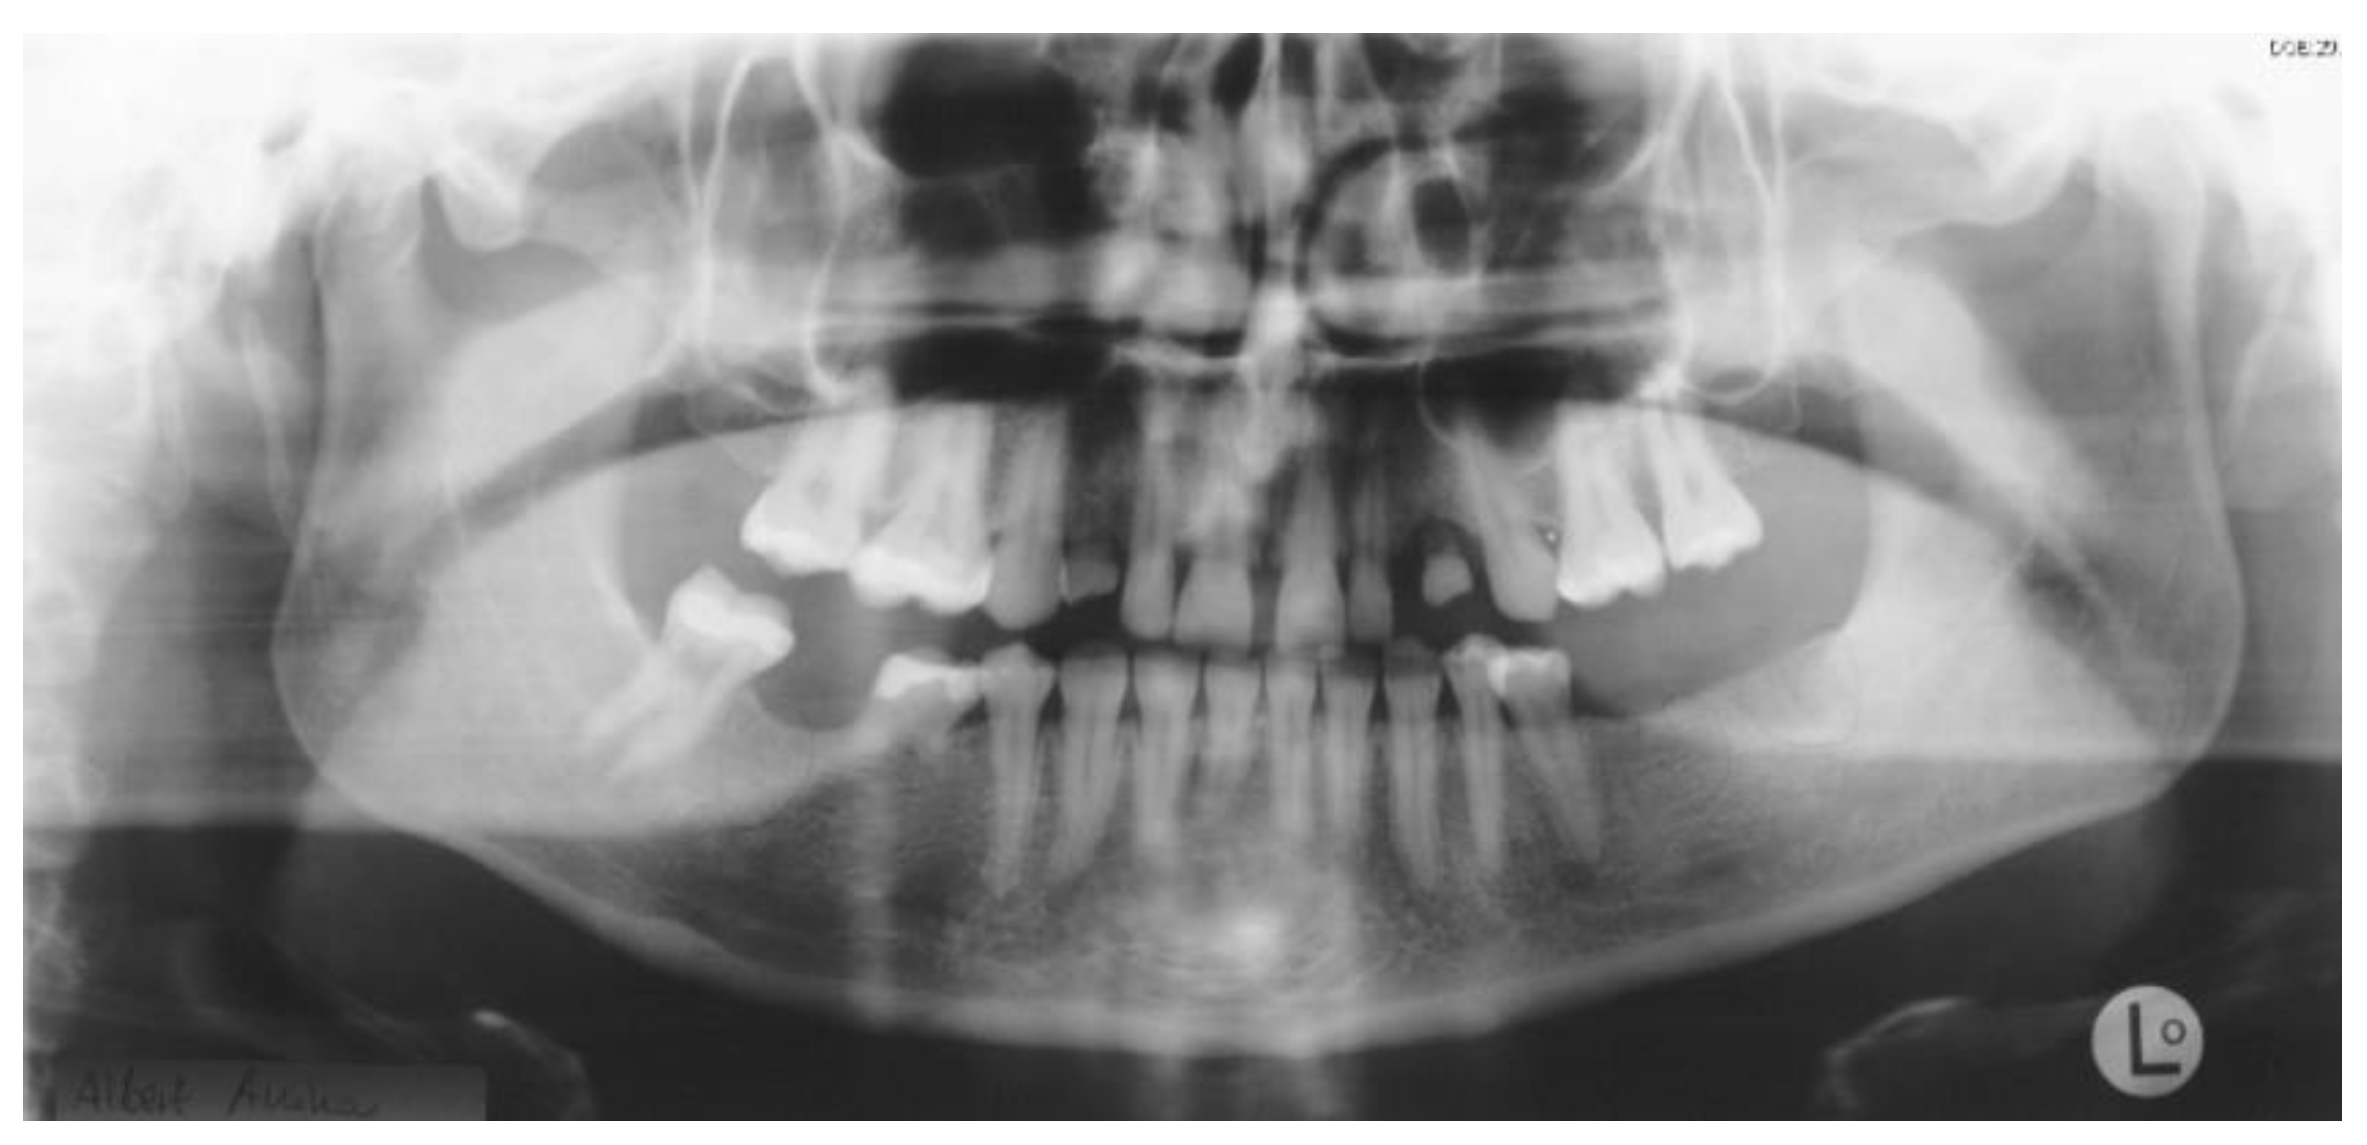

2.1. Case One